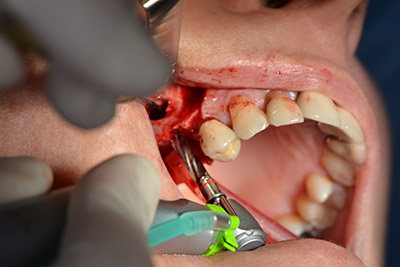

The next programmed position is the placement of the implant and in our practice it is preset to a force of 32 Ncm (Fig. 12).